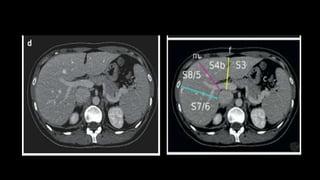

• Right hepatic vein divides the

right lobe into anterior and

posterior segments.

• Left hepatic vein divides the left

lobe into left medial and left

lateral sections.

• The portal vein divides the liver

horizontally into upper and lower

segments.

• There are eight liver segments.

• Segment IV is divided into segment IVa and IVb according to Bismuth.

• The numbering of the segments is in a clockwise manner.

• Segment I (the caudate lobe) is located posteriorly.

• It is not visible on a frontal view.